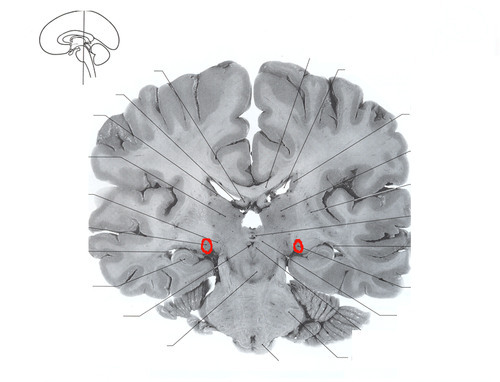

Left circle

Lateral geniculate nucleus

synapse point for optic nerve before moving to visual cortex; part of geniculate body

thalamic relay nucleus for visual pathway

medial geniculate nucleus

fxn: receives auditory info from inferior colliculi

sends info to auditory cortex

Q

Right circle